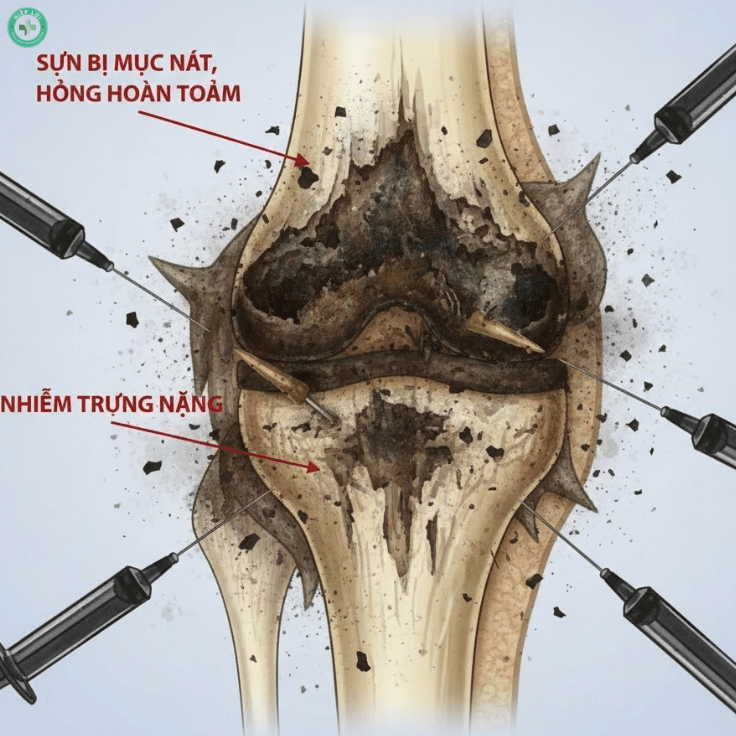

7. Lạm dụng thuốc giảm đau và Corticoid bừa bãi

Nhiều bệnh nhân khi đau thường tự ý mua "thuốc tễ", "thuốc nam" không rõ nguồn gốc hoặc lạm dụng tiêm giảm đau nhanh tại các cơ sở không chuyên khoa. Thực chất, các loại thuốc này thường chứa Corticoid liều cao. Chúng làm giảm đau tức thì nhưng lại gây ra tác dụng phụ khủng khiếp: ức chế quá trình tạo xương, làm mỏng sụn và gây giòn xương. Kết quả là sau một thời gian hết đau giả tạo, khớp gối sẽ sụp đổ hoàn toàn (hoại tử xương), khiến việc điều trị sau này cực kỳ phức tạp.

Biến chứng hủy hoại khớp do tự ý tiêm giảm đau Corticoid